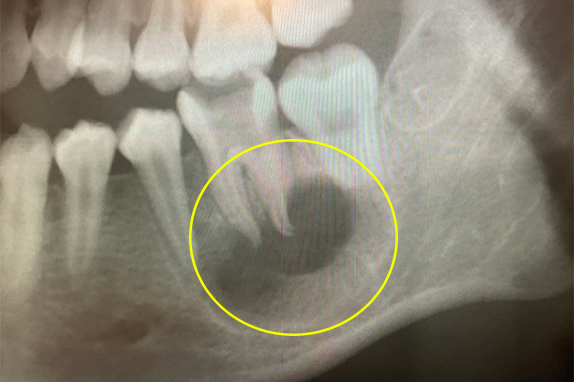

CASE 07 マイクロエンド(精密根管治療)+歯根周囲掻爬(歯周外科)

-

- 主訴

- 歯ぐきがよく腫れる(10代女性)

-

- 回数期間

- 7回 約1年半

-

- 治療法

- マイクロエンド(精密根管治療)、歯根周囲掻爬(歯周外科)

-

- 治療費用

- 約35万円(税抜)

歯ぐきがよく腫れる主訴で来院。レントゲン写真の術前を見ると大きな影が確認できます。この部分に嚢胞(のうほう)がある状態です。マイクロエンドと歯根周囲掻爬(歯周外科)をすることで改善したケースです。

<リスク・副作用>

治療後は痛み、腫れ、痺れなどの副作用が生じる場合があります。症状が再発する可能性があります。